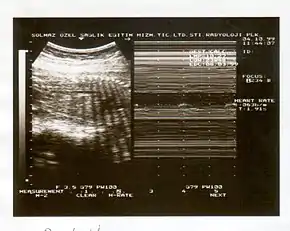

A biophysical profile (BPP) is a prenatal ultrasound evaluation of fetal well-being involving a scoring system,[1] with the score being termed Manning's score.[2] It is often done when a non-stress test (NST) is non reactive, or for other obstetrical indications.

The BPP has five components: four ultrasound (US) assessments and an NST. The NST evaluates fetal heart rate and response to fetal movement. The five discrete biophysical variables are:

- Fetal heart rate

- Fetal breathing

- Fetal movement

- Fetal tone

- Amniotic fluid volume